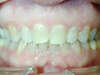

Vues avant le traitement